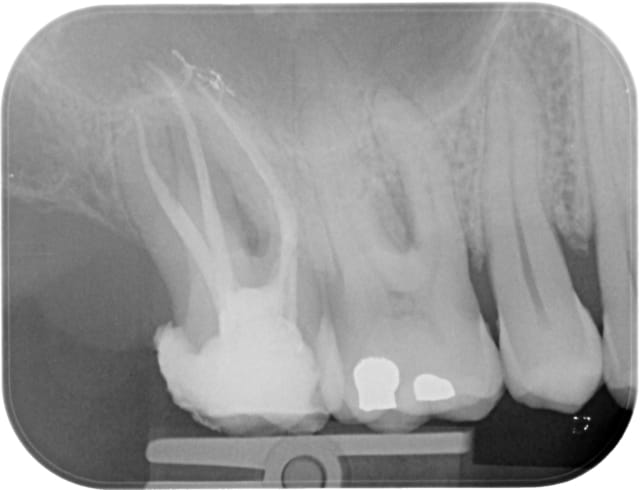

Un autre cas plus sympa, toujours au Wave One primary.

Ca marche super bien, par contre comme je pensais un peu ça ne fait pas gagner un temps inoui... si sur une endo d'une heure vous passez 5 minutes sur la rotation continue en elle même, vous en passerez peut être 1'30 (totalement pifométrique) sur le wave one, ce n'est pas ça qui va changer énormément la durée du rendez vous.

Waveone17 pr  q2fxwb - Eugenol

Waveone17post fcxjf1 - Eugenol

Et l'endo est très belle, bravo.